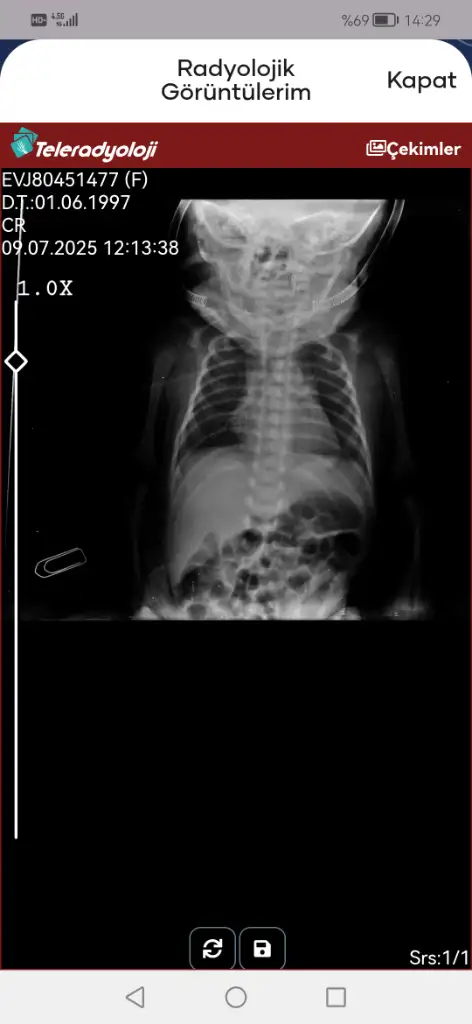

Evet entübasyon hortumu görünmüyor iki hortum olmalıydı ağzında. Entübeden ayrılması da iyi bir şey süt de azıcık gaz yapmış hatta bebişe. Süt aldıkça bu değerler toparlanır. Kan gazına göre bebeğiniz solunumu tölere edebiliyor diyebiliriz bunlar güzel haberler

• Screenshot_20250709_142908_tr.gov.saglik.enabiz.webp

Screenshot_20250709_142908_tr.gov.saglik.enabiz.webp

16,8 KB · Görüntüleme: 22